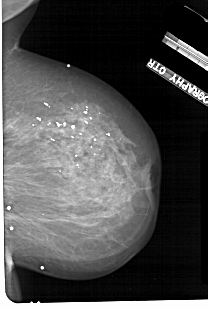

A_1114_1.RIGHT_MLO

RIGHT_MLO LINES 4621 PIXELS_PER_LINE 3106 BITS_PER_PIXEL 12 RESOLUTION 43.5 NON_OVERLAY